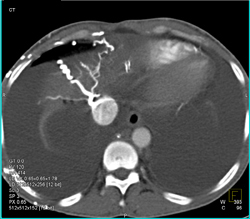

Diagnosis

Normal MIP of the Lung